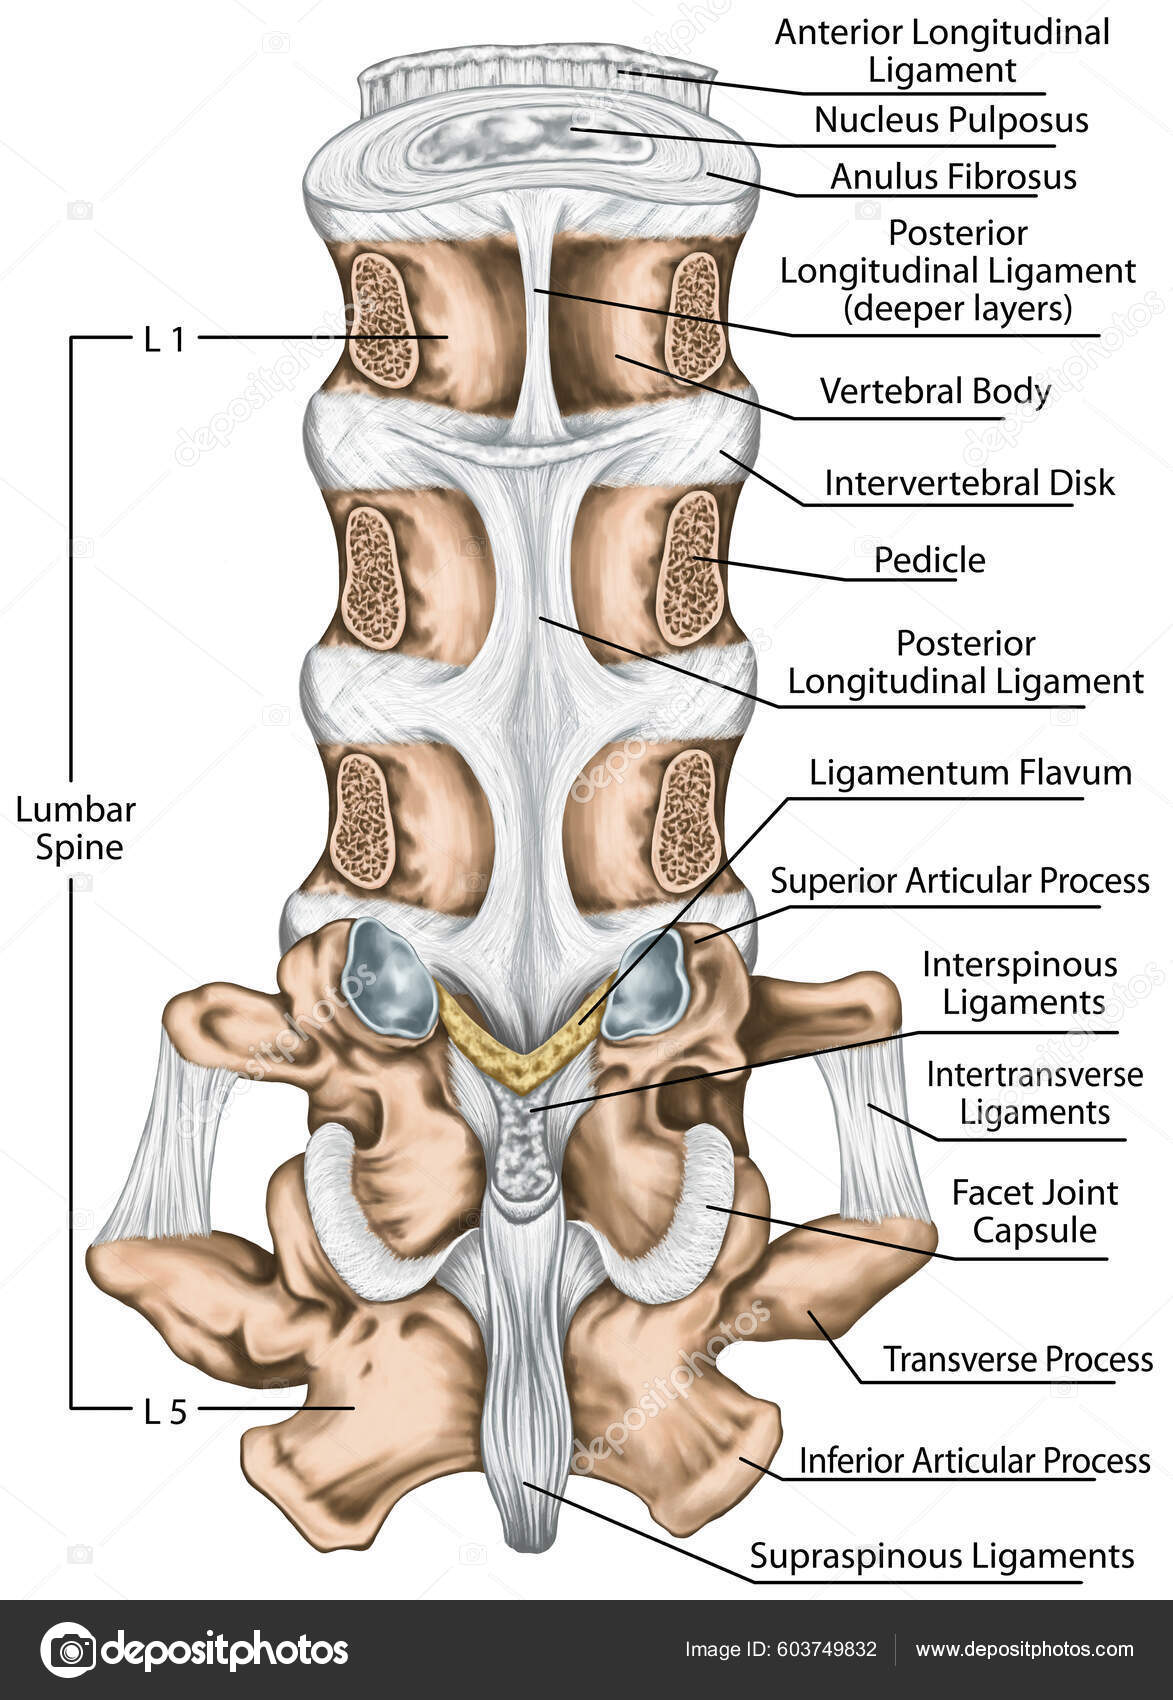

Ligaments Lumbar Spine Structure Ligaments Surrounding Lumbar Spine Posterior Longitudinal — Stock Photo © stihii #603749832

DOCS - The interspinous ligament is located between the spinous processes of adjacent vertebrae in the spine. It extends from the base of one spinous process to the apex of the next,

Pure Health - Anatomy 101 - Supraspinous ligament and interspinous ligament 📚 The supraspinous ligament and interspinous ligament work together to limit flexion of the spine by limiting separation of the spinous